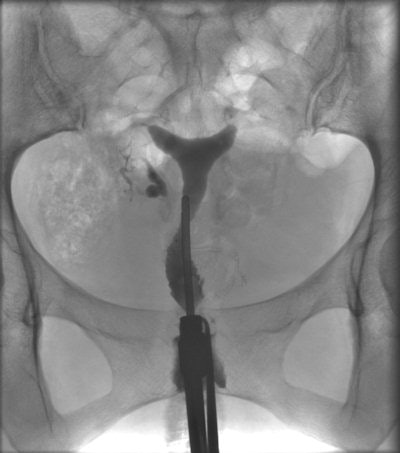

Schankath and colleagues don't advise that HSG should be tossed out -- it's a safe, low-cost test and, with the application of propofol sedation, a well-tolerated procedure for tubal assessment. However, it should be performed at the end of the infertility investigation protocol.

"The relatively low percentage (21%) of pathological exams in our population underlines the need for good patient preselection," they wrote. "The high false-positive rate for proximal tubal occlusion (39%), probably due to tubal spasm, demonstrates the importance of antiperistaltic agents and delayed imaging."

"This could mean that the indication for HSG was too broad or that there could even be a therapeutic effect of the HSG procedure, i.e., improved patency of the fallopian tube because of the flushing during the examination," they wrote.